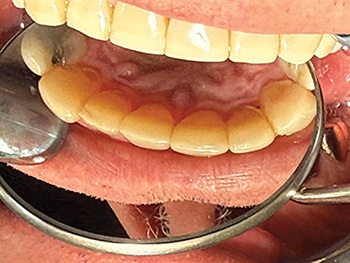

At presentation, the patient showed significant wear on the anterior teeth, with the lower incisors nearly absent from view and occlusion severely flattened (Fig. 1). The maxillary bicuspids sat buccal to their lower counterparts. The patient reported no pain, and radiographs showed no active pathology.

Fig. 1: Pre-op wear